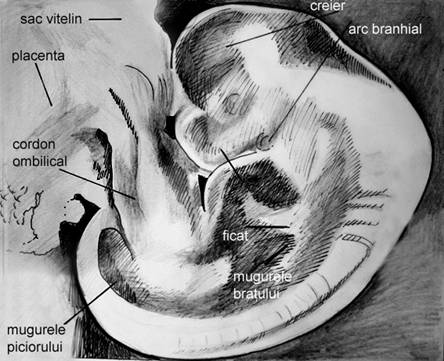

Fig. nr.106. Aspecte morfologice ale sarcinii normale la 9 saptamani ( schematic )

Fig. nr.107 Dezvoltarea embrionului si a anexelor , la o sarcina de 7 saptamani.

( adaptat dupa Merz[13])